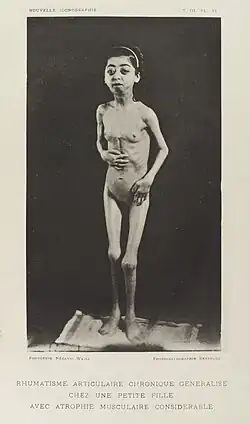

Disuse causes rapid muscle atrophy and often occurs during injury or illness that requires immobilization of a limb or bed rest. Depending on the duration of disuse and the health of the individual, this may be fully reversed with activity. Malnutrition first causes fat loss but may progress to muscle atrophy in prolonged starvation and can be reversed with nutritional therapy. In contrast, cachexia is a wasting syndrome caused by an underlying disease such as cancer that causes dramatic muscle atrophy and cannot be completely reversed with nutritional therapy. Sarcopenia is age-related muscle atrophy and can be slowed by exercise. Finally, diseases of the muscles such as muscular dystrophy or myopathies can cause atrophy, as well as damage to the nervous system such as in spinal cord injury or stroke. Thus, muscle atrophy is usually a finding (sign or symptom) in a disease rather than being a disease by itself. However, some syndromes of muscular atrophy are classified as disease spectrums or disease entities rather than as clinical syndromes alone, such as the various spinal muscular atrophies.

The predominant symptom is increased weakness which may result in difficulty or inability in performing physical tasks depending on what muscles are affected. Atrophy of the core or leg muscles may cause difficulty standing from a seated position, walking or climbing stairs and can cause increased falls. Atrophy of the throat muscles may cause difficulty swallowing and diaphragm atrophy can cause difficulty breathing. Muscle atrophy can be asymptomatic and may go undetected until a significant amount of muscle is lost.[2]

Intrinsic muscle diseases

Muscle diseases, such as muscular dystrophy, amyotrophic lateral sclerosis (ALS), or myositis such as inclusion body myositis can cause muscle atrophy.[13]

Outcomes of muscle atrophy depend on the underlying cause and the health of the patient. Immobility or bed rest in populations predisposed to muscle atrophy, such as the elderly or those with disease states that commonly cause cachexia, can cause dramatic muscle atrophy and impact on functional outcomes. In the elderly, this often leads to decreased biological reserve and increased vulnerability to stressors known as the "frailty syndrome."[3] Loss of lean body mass is also associated with increased risk of infection, decreased immunity, and poor wound healing. The weakness that accompanies muscle atrophy leads to higher risk of falls, fractures, physical disability, need for institutional care, reduced quality of life, increased mortality, and increased healthcare costs.[3]